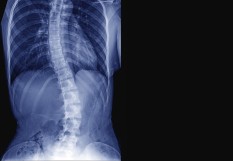

Le Dr Yves Cotrel est décédé le 29 janvier 2019, à 9h15, à l’âge de 93 ans. Il est connu pour avoir mis au point, avec le Pr Jean Dubousset un dispositif implantable novateur qui, en 1983, a modifié la prise en charge chirurgicale de la scoliose.

Cette instrumentation (dénommée instrumentation CD pour Cotrel-Dubousset) permet, en effet, de corriger la déviation de la colonne vertébrale et de consolider le segment redressé avec une grande stabilité. Cela évite au patient le port de plâtre et de corset qui était jusqu’à présent nécessaire pendant de près d’un an après l’intervention. Plus de deux millions de patients dans le monde ont déjà bénéficié de cette méthode. "L’histoire de ma vie professionnelle a été jalonnée d’événements imprévus et parfois traumatisants…. Alors que je me destinais à la carrière d’obstétricien et prévoyais de m’installer en Bretagne, je fus subitement envoyé à Berck, dans le Nord de la France, pour y devenir chirurgien orthopédiste. Je devais y rester trente ans", affirmait ainsi le Dr Cotrel. Né le 27 avril 1925 à Dinan, Yves Cotrel va consacrer sa vie à la scoliose, en tant que clinicien (à l’Institut Calot de Berck), puis en tant que chercheur, suite à un triple arrêt cardiaque qui, en 1975, l’oblige à cesser toute activité professionnelle. C’est à partir de ce moment-là, et grâce au techniques américaines avec lesquelles il s’est familiarisé, qu’il invente une toute nouvelle instrumentation métallique implantable. Fin 1982, il sollicite Jean Dubousset, qui exerce à l'hôpital Saint-Vincent de Paul à Paris, afin d'essayer d'opérer un malade avec le nouveau dispositif. La première opération a lieu le 21 janvier 1983, sur un adolescent. "Yves Cotrel, qui était présent dans la salle d'opération mais ne pouvait être trop près de l'opérateur à cause du pacemaker qu'il portait, notait tout, comme il l'a fait au cours des interventions suivantes", racontait Jean Dubousset en 2015 dans un mémoire réalisé pour l'Académie de chirurgie. "Le malade fut levé au troisième jour sans plâtre ni corset", s'était-il souvenu. D'abord testée sur des enfants et des adolescents, la technique a ensuite été étendue à l'adulte. Par la suite, le Dr Cotrel parcourt le monde afin de former les chirurgiens à cette nouvelle technique. En 1999, avec l'accord de son épouse Marie-Lou et de leurs huit enfants, il crée, sous l'égide de l'Institut de France, une fondation de recherche sur les pathologies de la colonne vertébrale, qui porte son nom. "Je désire que les moyens, dont je puis disposer aujourd’hui, servent à poursuivre la recherche au bénéfice d’une pathologie à laquelle j’ai reçu la mission de travailler... ". La fondation Cotrel soutient aujourd'hui plus de 60 équipes de chercheurs dans le monde pour relever le défi lancé par le Dr Yves Cotrel à la scoliose "idiopathique" afin qu’elle livre enfin le secret de ses causes et de ses mécanismes d'évolution.